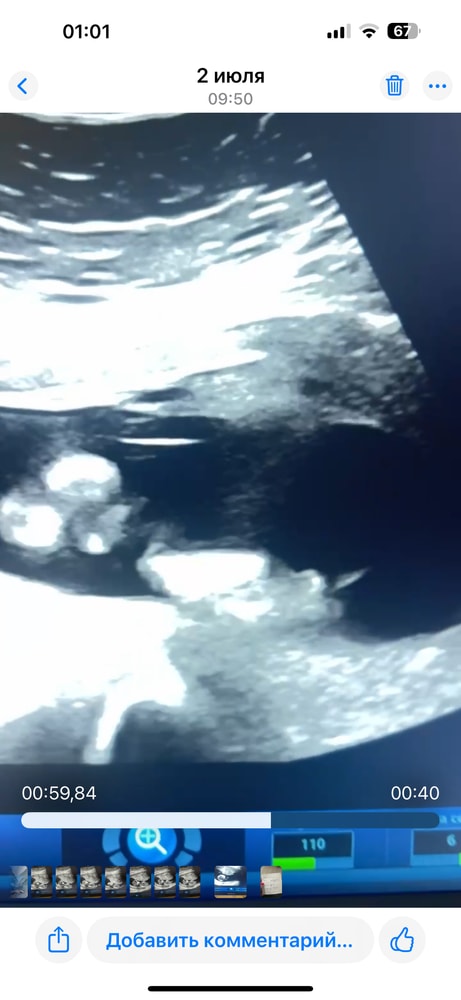

Девочки ,а кто понимает ?Помогите определить по половому бугорку

Пол малыша

Ну может предположительно кто как считаете ?)

Мне кажется у вас мадам 😻

Похоже на мальчика у вас